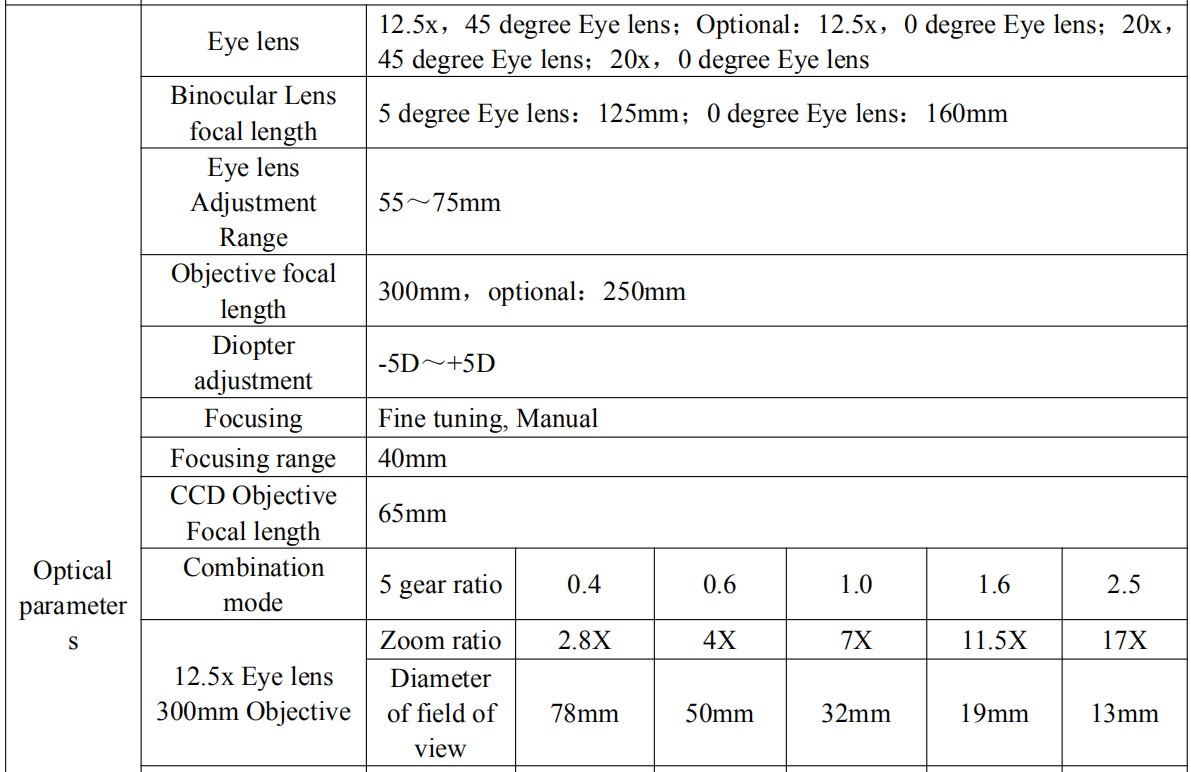

Binocular eyepiece technical parameter